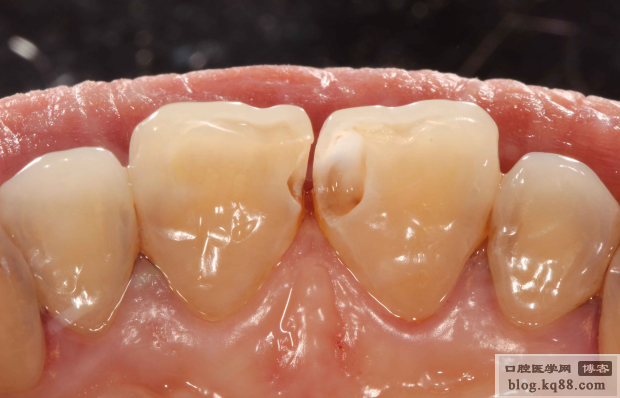

去腐